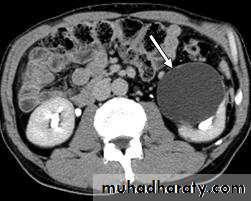

IVU :-* Nephrogram shows filling defect .

*Displacement , elongation & stretching of PCS which depend on size and site of the cyst .

US :-

shows echo-free cystic lesion with posterior enhancement.